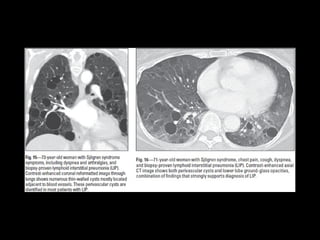

IIP raras LIP • Benigna •Idiopática es rara • Asociada a SS, VIH, enferemedad autoinmune tiroides, enfermedad de castleman M, 50 Disnea tos, fiebre artralgias, 80% disproteinemias igG igM

• Infiltración delinfocitos e histiocitos engrosando septos

LIP CT • Vidrioesmerilado • Nódulos • Engrosamiento septos y peribroncovascular • *Quistes 80% LI DD: NSIP celular • DD: histiocitosis de langerhans, linfangioleiomiomatosis, enfisema, DIP,